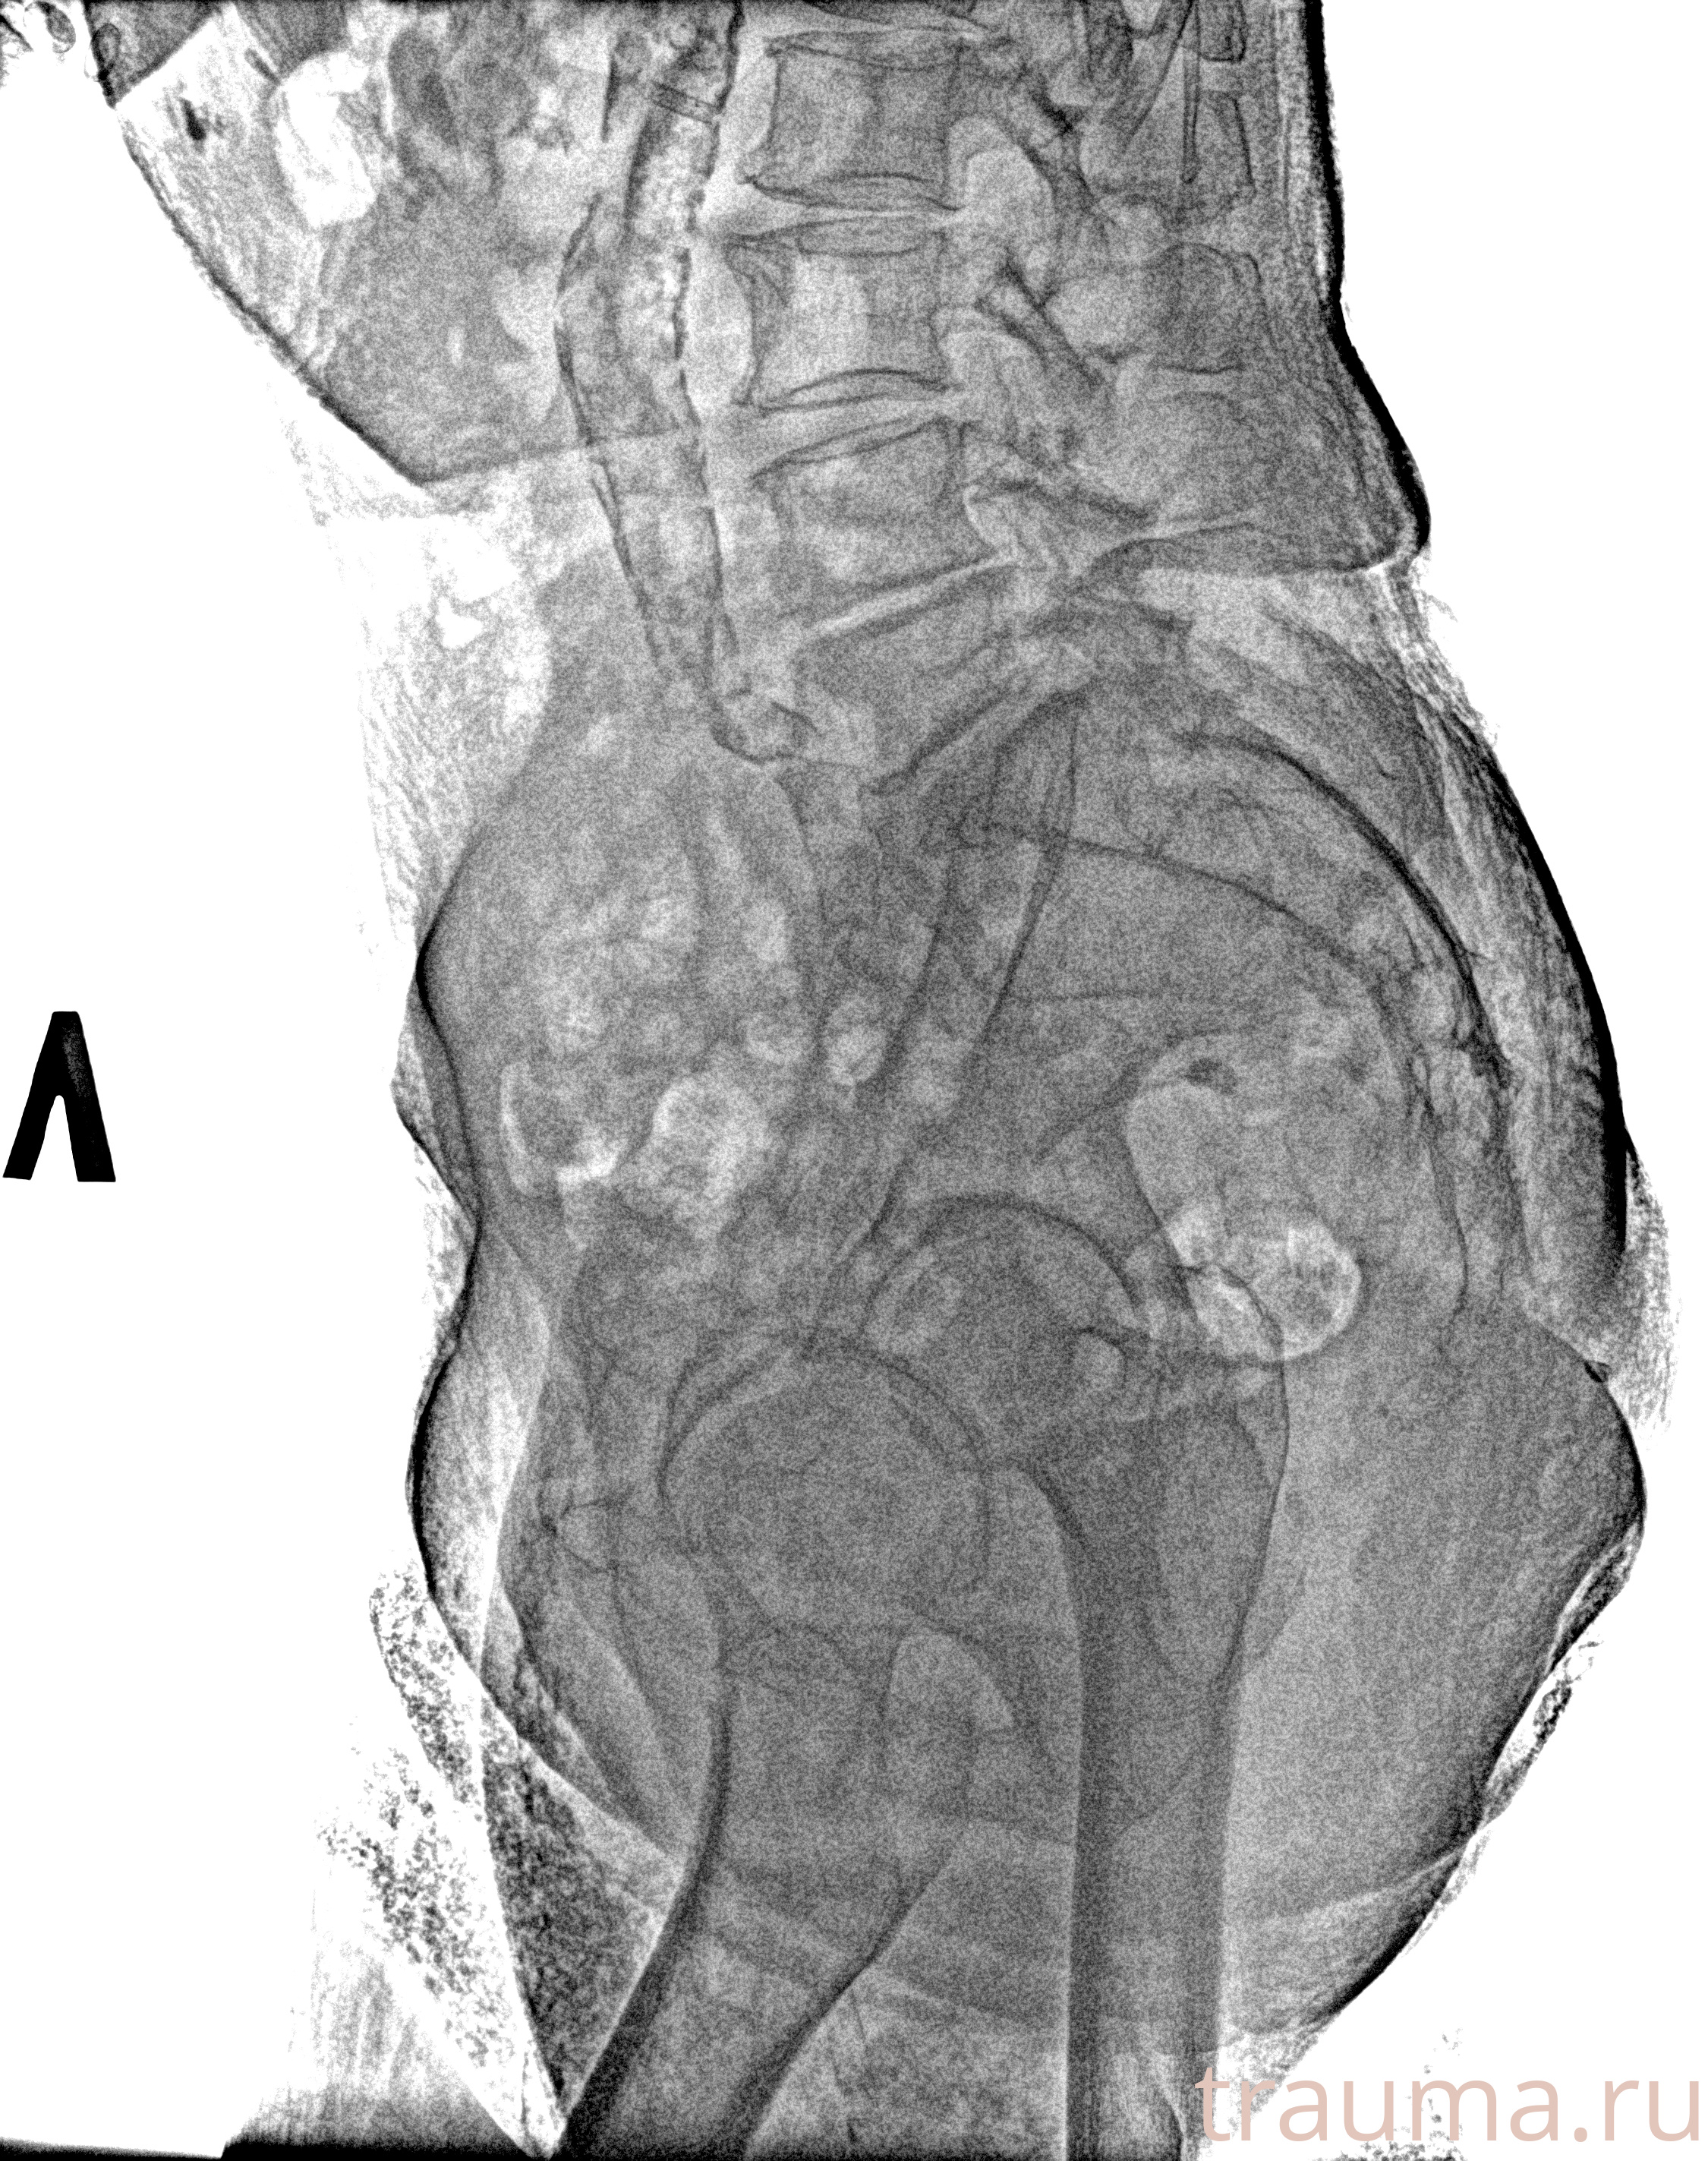

Рентген на дому: по вашему адресу приезжает врач-рентгенолог, травматолог-ортопед с мобильным рентгеновским аппаратом, проводит диагностику травмы или заболевания, делает необходимые рентгенограммы, дает рекомендации по дальнейшему лечению. Получить качественные снимки в домашних условиях возможно благодаря уникальной методике, разработанной МосРентген Центром для института  Склифосовского